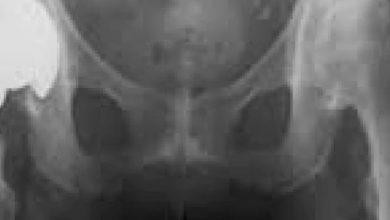

Total kalça protezi rehabilitasyonu

Kalça ekleminin ilerleyen dejenerasyonuna koksartroz adı verilir. Koksartroz kalça ekleminde ağrı ve hareket kısıtlılığı ile karakterize dejeneratif bir hastalıktır. Hastalığın…